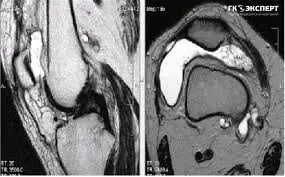

УЗД коліна — достатньо точний метод діагностики патології м’ягких тканин суглоба. УЗД дозволяє бачити запалення, уточнювати стан синовіальнї оболонки, об’єм рідини в коліні, її локалізацію і ті.

Проліферація синовіальної оболонки коліна при кісті Бейкера (фото нижче)

Оцінка стану суглобового хряща коліна, що вкрай важливо при артрозі (фото нижче).

Оцінка кровотоку в синовіальній оболонці колінного суглоба